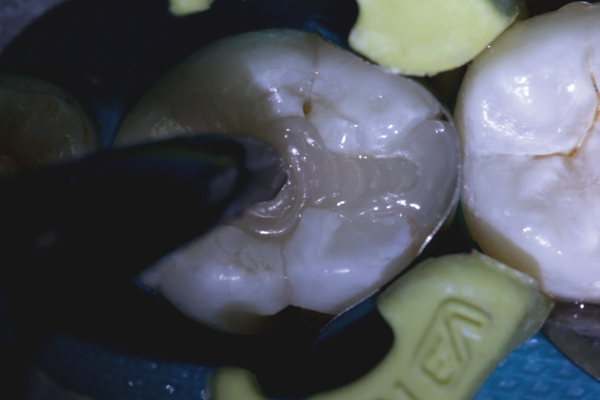

(5.) Placement of composite into tooth No. 19.

Figure 5

Higher viscosity bulk-fill composites can be used up to the occlusal surface, however. Two clinical cases using the bulk-fill composites Tetric EvoCeram Bulk Fill and SonicFill are presented in Figure 2 through Figure 6. Limitations when placing a high-viscosity bulk-fill composite include difficulty of condensing and esthetic restraints. Condensing a high-viscosity resin composite ensures adequate adaptation to the tooth preparation and sufficient interproximal contacts. Condensing 4 mm of composite is more difficult than condensing 2 mm. To ensure adequate interproximal contacts, a sectional or circumferential matrix with an inciso-gingival curvature can be used to obtain a tight area of contact gingival to the marginal ridge. A ring should be used to help separate the teeth and improve the tightness of the contact area.